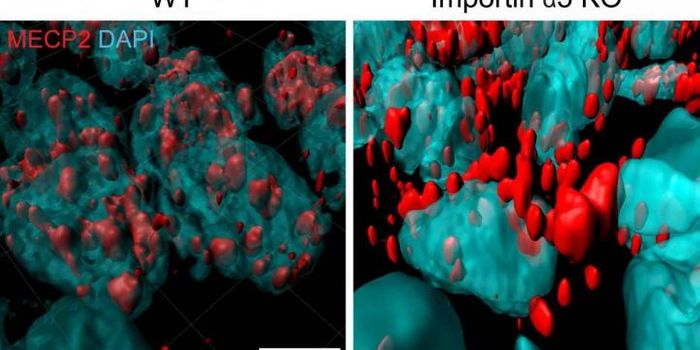

JUL 04, 2021Genetics & GenomicsRett syndrome is a neurological disorder that mostly affects girls; affected individuals develop normally until they're ...